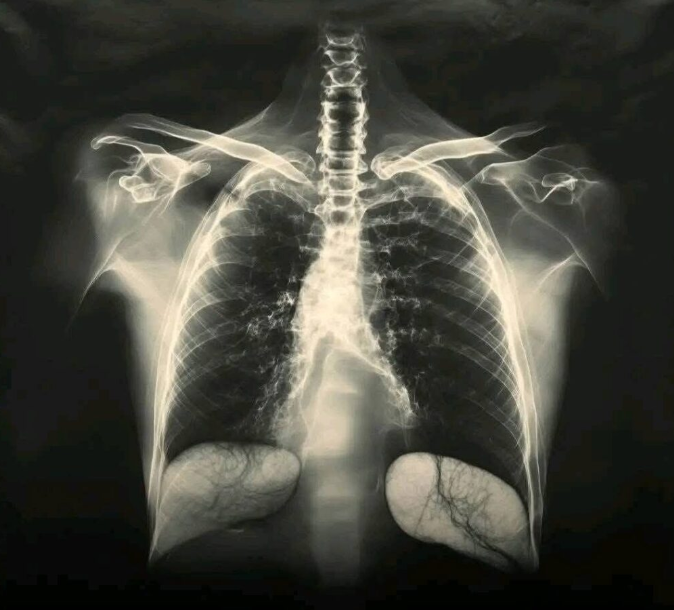

Szczepionka przeciw COVID-19 a zdrowie płuc – co mówi nauka

Od początku kampanii szczepień przeciw COVID-19 regularnie powraca pytanie: czy szczepionka może szkodzić płucom? Wiele osób zgłasza po szczepieniu uczucie duszności lub dyskomfortu w klatce piersiowej, co naturalnie budzi niepokój. Ponieważ pandemia od samego początku była silnie związana z chorobami układu oddechowego, obawy dotyczące zdrowia płuc są zrozumiałe i zasługują na rzetelne, spokojne wyjaśnienie oparte na faktach naukowych.

Szczepionki przeciw COVID-19, zarówno te oparte na technologii mRNA, jak i szczepionki wektorowe, mają jedno podstawowe zadanie: pobudzić układ odpornościowy do rozpoznawania wirusa. Nie zawierają one żywego wirusa ani żadnych substancji, które mogłyby bezpośrednio atakować lub uszkadzać tkanki płucne. Ich działanie ogranicza się do przekazania informacji immunologicznej, dzięki której organizm uczy się reagować szybciej i skuteczniej w przypadku kontaktu z prawdziwym wirusem.

Światowe instytucje zdrowia publicznego nieustannie monitorują bezpieczeństwo szczepionek. Analizowane są miliony podanych dawek, a zgłoszenia działań niepożądanych są skrupulatnie oceniane. Do tej pory nie ma wiarygodnych danych naukowych wskazujących na trwałe pogorszenie funkcji płuc po szczepieniu przeciw COVID-19. Bardzo rzadkie przypadki poważnych problemów oddechowych są zazwyczaj związane z ciężkimi reakcjami alergicznymi, które występują sporadycznie i są szybko leczone w punktach szczepień.